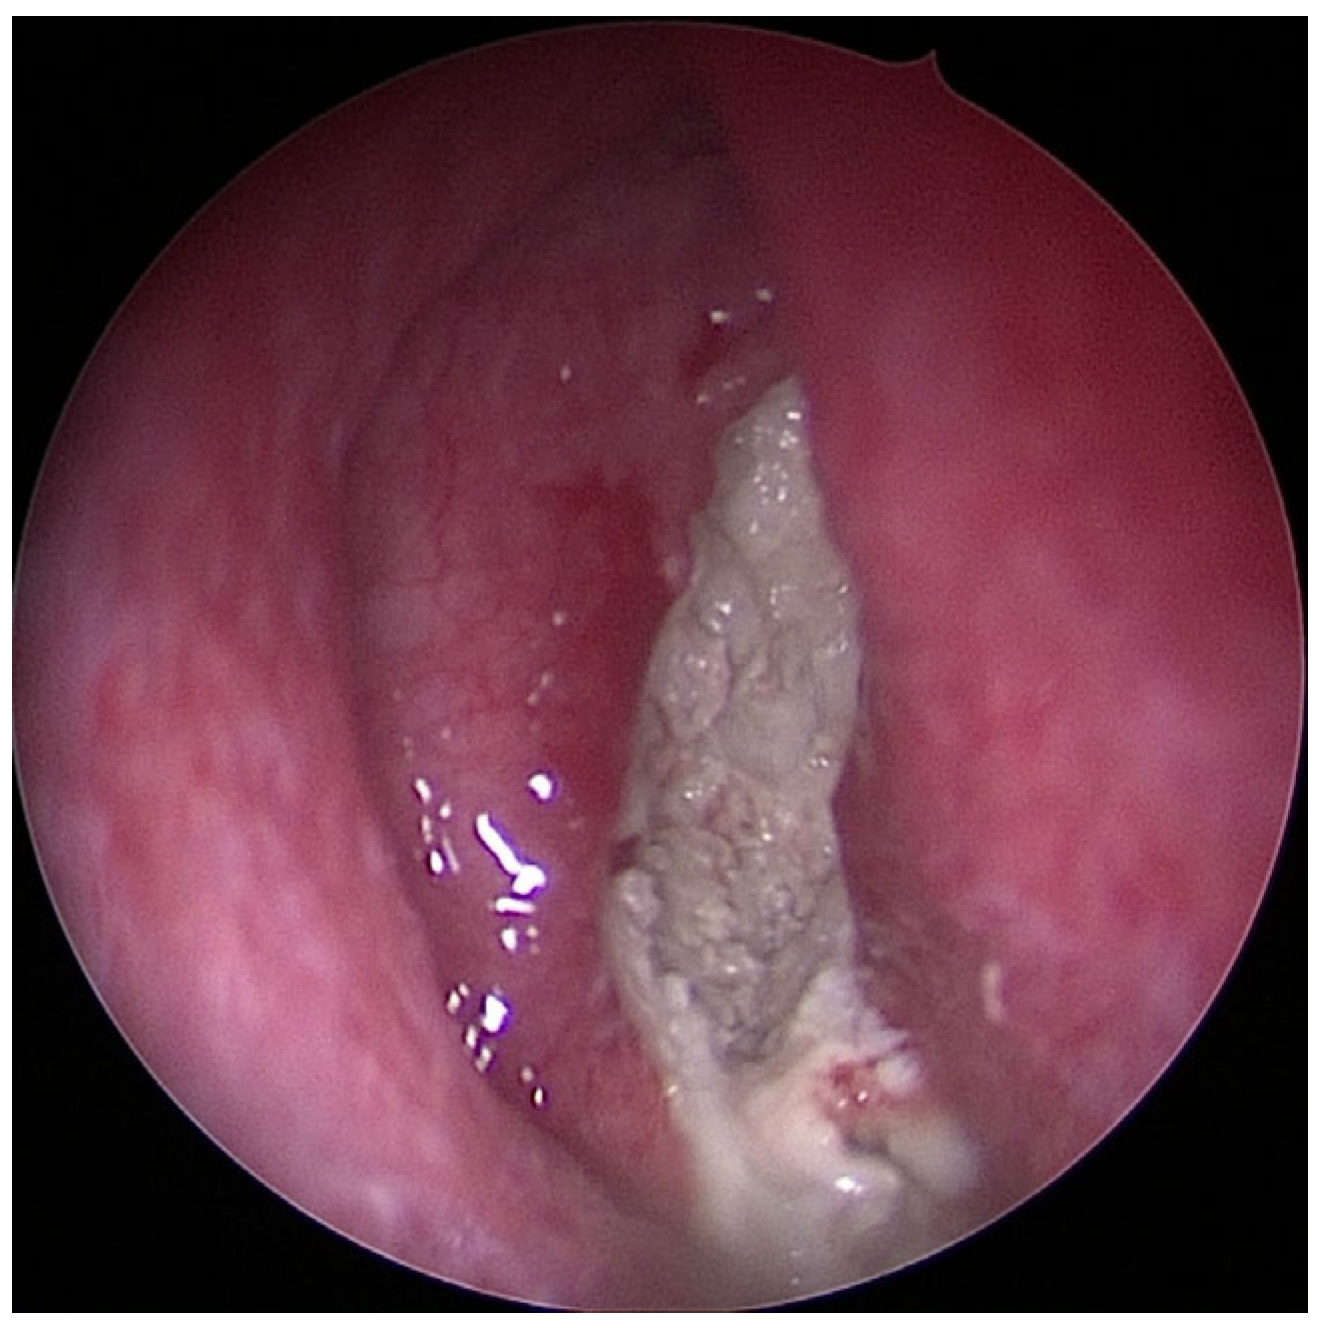

Figure 3. Image of chronic purulent odontogenic maxillary sinusitis with fungal superinfection via FESS (endoscope with straight–forward optic 0°).